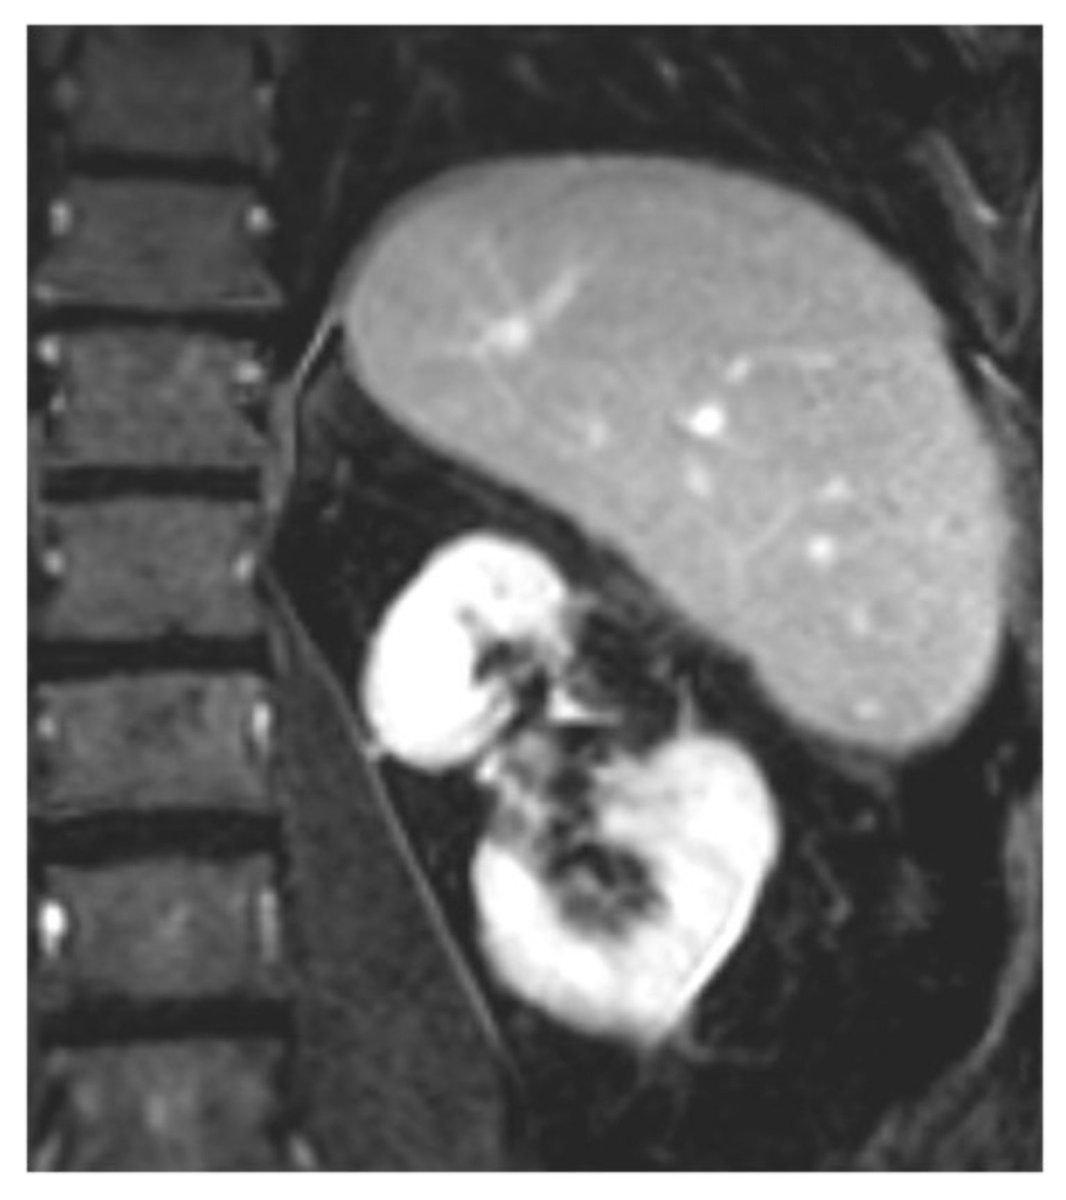

Interventional Radiology has a leading responsibility for patients with #HCC.

Congrats to my colleague @FZIslamMD for leading our latest pub, which highlights the importance of multidisciplinary management for HCC + the critical footprint of Interventional Radiology across multiple timepoints. 📝 dovepress.com/real-world-ana… @BeauToskichMD @MayoClinicFL_IR